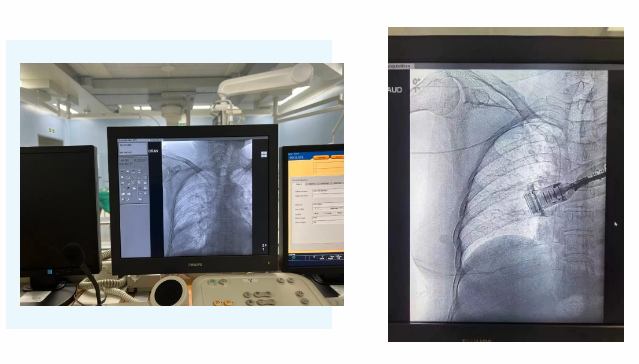

在麻醉手術(shù)中心的配合下,手術(shù)首先由韓海靜護士長在超聲引導下應用“塞丁格”法穿刺將針尖一樣細的導絲送入血管,術(shù)中在DSA透視下將導管沿著血管送達上腔靜脈,尖端精準定位至上腔靜脈開口處。隨后,胸腔外科支亞男主治醫(yī)師在穿刺點下方取2厘米小切口內(nèi)進行上臂港囊袋和隧道的制作及導管與港座連接,最后進行港體埋植及皮內(nèi)縫合,使患者切口隱蔽美觀創(chuàng)傷小,術(shù)中出血量極少。手術(shù)在X片影像留影,最終手術(shù)順利完成。